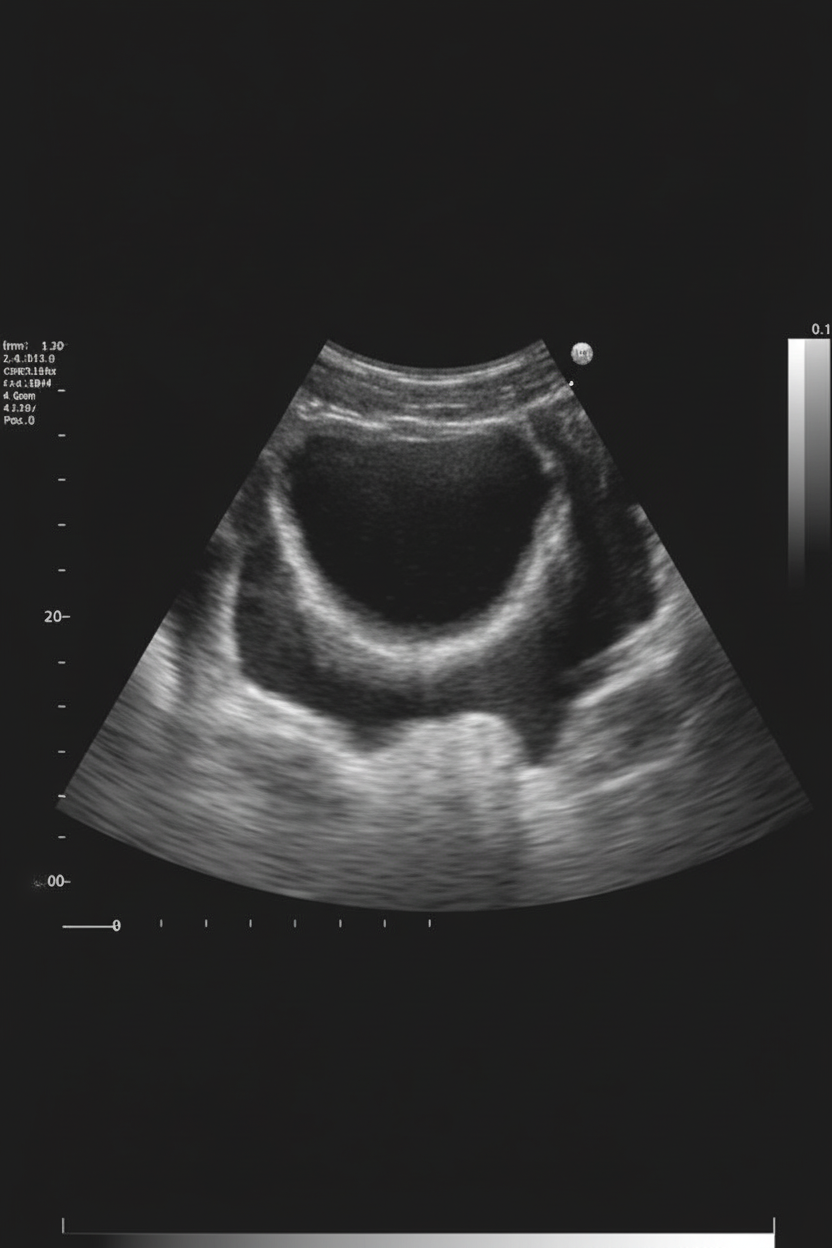

The congenital anomaly of the gallbladder shown in the image is:

Explanation: ***Phrygian cap*** - This congenital anomaly shows the **gallbladder fundus folded back** onto the body, creating a characteristic **cap-like appearance** resembling the ancient Phrygian cap. - It is a **benign developmental variant** that is usually an **incidental finding** with no clinical significance and requires no treatment. *Septum* - A gallbladder septum appears as a **thin membrane** dividing the gallbladder lumen into compartments, not a folding of the fundus. - It creates **internal partitions** within the gallbladder rather than the external contour change seen in Phrygian cap. *Diverticulum* - A gallbladder diverticulum presents as an **outpouching** or **small sac** extending from the main gallbladder wall. - It appears as an **additional chamber** or **pouch**, not a folded fundus configuration. *Normal* - A normal gallbladder has a **smooth pear-shaped outline** with the fundus extending beyond the body without folding. - The **fundus, body, and neck** maintain their typical anatomical relationships without structural variants.